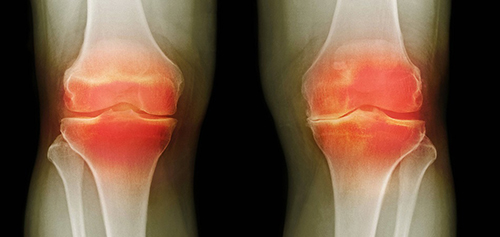

La causa principal del daño articular es la acumulación de cristales de sal en las articulaciones debido a una circulación sanguínea deficiente y a una mala circulación del líquido sinovial:

- Los cristales de urato son sales del ácido úrico que provocan la gota.

- Los osteofitos son sales calcificadas responsables del 97% de las demás enfermedades articulares y de la columna, como la artritis, artrosis, osteocondrosis, osteoporosis, reumatismo, bursitis e incluso quistes sinoviales.

Estas sales, al depositarse en la superficie de la articulación, actúan como papel de lija, dañando los tejidos circundantes, los huesos y el cartílago. A medida que los cristales crecen, comienzan a dañar los tejidos musculares, los tendones, los vasos sanguíneos y los capilares, provocando inflamación, infección, hinchazón y dolor intenso.

Las enfermedades articulares que en colombia se intentan diagnosticar por separado, hace tiempo que en Japón se unificaron bajo una sola condición: "Depósito de sales en las articulaciones". Esta condición incluye:

- Gota

- Artritis

- Artrosis

- Osteocondrosis

- Reumatismo

- Osteoporosis

- Bursitis

- Sinovitis

- Quiste sinovial

Esta es una lista muy resumida, pero las demás enfermedades son simplemente subtipos de estas nueve patologías principales. Por ejemplo, la coxartrosis es un subtipo de artrosis, y así sucesivamente.